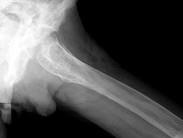

问题 男,60岁,左股骨痛1年余,结合图像,最可能的诊断是?(?)

选项 A.骨纤维异常增殖症 B.Paget病 C.髋关节结核 D.股骨头缺血坏死 E.化脓性骨髓炎

答案 B